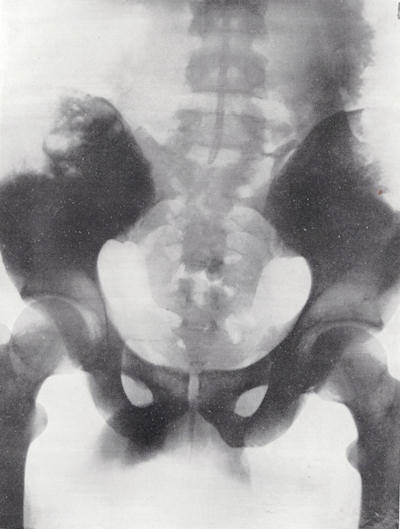

This new device was marketed as the Potter-Bucky diaphragm and was announced in February 1917 at the ARRS.4 Potter demonstrated the use of this apparatus to show the lumbar spine, hips and pelvis, and renal calculi. It is famously recorded that at one meeting after Potter had shown his work, one radiologist was so surprised by the quality of the images that he accused Potter of touching up the negatives!

There was a certain delay in making the apparatus commercially available because of discussions about the priority of the discovery. However, in 1921 the Potter-Bucky diaphragm was finally marketed and was immediately accepted by the radiological profession. Whilst the image of the pelvis from 1921 is excellent, it should be noted that the exposure time was 12 seconds!